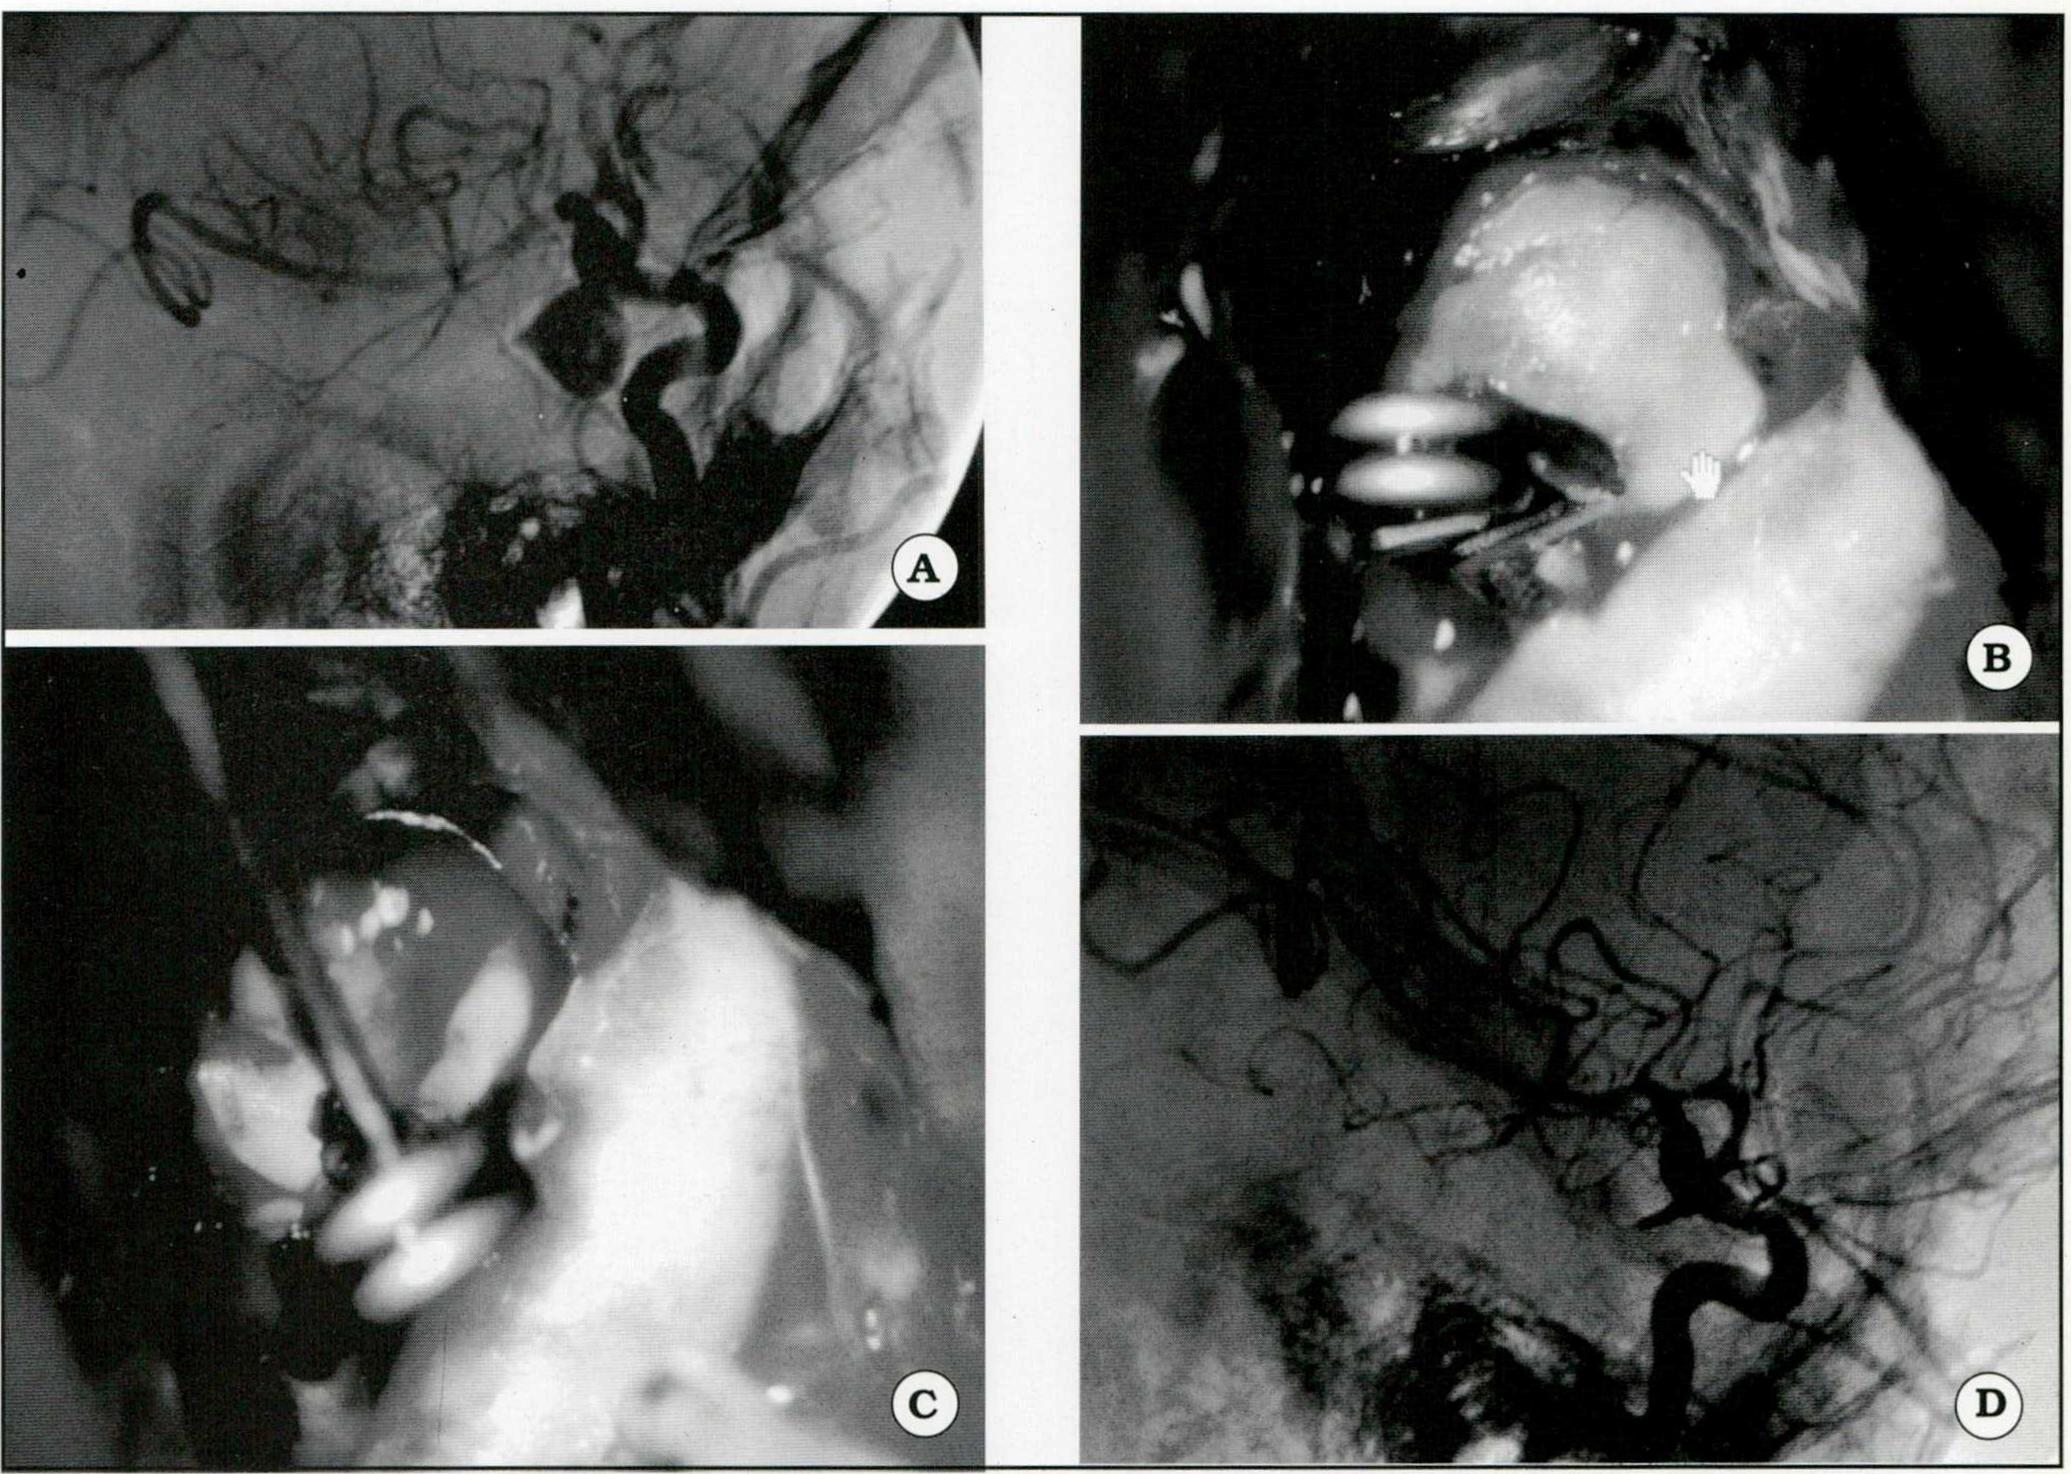

Se ejemplifican iconográficamente las siguientes situaciones:

- Aneurisma gigante de la ACI, correspondiente al segmento comunicante posterior. (Fig. 1).

Fig. 1. A. Angiografía que muestra un aneurisma gigante del segmento comunicante posterior. B. Imagen intraoperatoria. Se observa el clipado del cuello aneurismá tico. C. Clipado del aneurisma. Se realizó punción del saco, maniobra cuyas ventajas se describen en el texto. D. Control angiográfico postoperatorio.